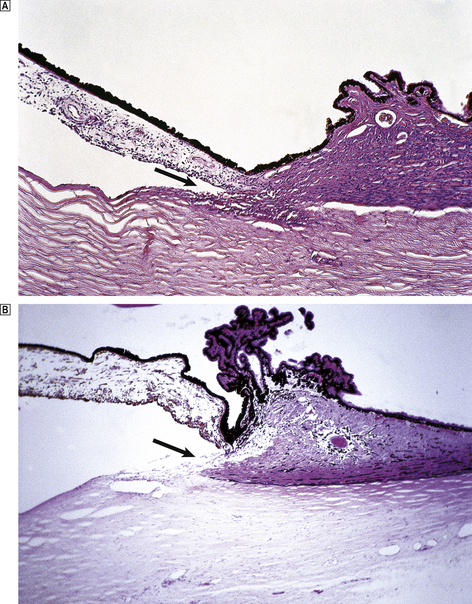

Acute disseminated encephalomyelitis

Acute disseminated encephalomyelitis is an infrequent complication of measles, mumps and rubella infections, and may also occur following vaccination for smallpox and rabies. The onset of the disease is sudden, usually occurring 5–14 days after the initial infection or inoculation. This appears to be a T-cell-mediated delayed hypersensitivity response to a protein component of myelin, but the mechanism of sensitisation is unknown. The prognosis is good, with a complete recovery in 90% of cases.

Acute haemorrhagic leukoencephalitis is a related but more severe disorder which is accompanied by immune complex deposition in cerebral vessel walls and is usually rapidly fatal.

Fungal infections

Fungal infections of the nervous system are relatively uncommon; most occur as a consequence of haematogenous spread from the lungs, but direct spread of infection from the nose and paranasal sinuses also occurs. In the UK, most fungal infections of the CNS occur in immunosuppressed patients, but some organisms, for example Cryptococcus neoformans, are capable of producing disease in humans in the absence of any predisposing illness. Cryptococcal infection usually presents as a subacute meningitis in which the inflammatory reaction is often remarkably mild.

Opportunistic fungal infections with Candida albicans and Aspergillus fumigatus are usually accompanied by pulmonary infection. Both organisms may cause meningitis with haemorrhage due to vascular invasion, and characteristically produce multiple cerebral abscesses.

Mucormycosis is a rare fungal infection that particularly affects uncontrolled diabetics, producing a granulomatous mass in the paranasal sinuses that extends to involve directly the skull and frontal lobes. Vascular involvement is also common with this organism, resulting in cerebral infarction.

Parasitic infections

Parasitic infections of the CNS are uncommon except in countries in which human parasites are endemic. The most frequently encountered organisms are:

Toxoplasma gondii, which may be congenital

Plasmodium falciparum, causing one form of malaria

Trypanosoma rhodesiense, causing chronic meningoencephalitis

Entamoeba histolytica, causing solitary amoebic abscess

Taenia solium, causing cerebral cysticercosis

Echinococcus granulosus, causing solitary hydatid cyst

Toxocara canis, causing eosinophilic meningitis, with granulomas around larvae.

Infections in immunosuppressed patients

CNS infections are common in immunosuppressed patients, whatever the nature of the underlying disease. The main varieties are:

atypical mycobacteria

cytomegalovirus

papovaviruses

Candida albicans

Aspergillus fumigatus

Cryptococcus neoformans

Toxoplasma gondii

Entamoeba histolytica.

Many of these infections prove fatal, and a diagnosis is often difficult to establish prior to death. Multiple infections are not uncommon, particularly in the acquired immune deficiency syndrome (AIDS).

DEMYELINATING CONDITIONS

image Can be due to viral, chemical or immunological mechanisms

image Axons are preserved while myelin disintegrates

image Myelin fragments are phagocytosed by macrophages and esterified into neutral lipids

image Commonest demyelinating condition is multiple sclerosis, in which the mechanism of demyelination is unknown

image Remyelination does not occur to any significant extent

In the CNS, most axons and dendrites are ensheathed in myelin, which is formed from complex folds of oligodendrocyte cell membranes. CNS myelin differs slightly in structure and composition from peripheral myelin, but serves essentially the same functions:

to protect and insulate neuronal processes

to allow the rapid transmission of electrical impulses by saltatory conduction.

Most of the myelin in the CNS is located in the white matter, but neuronal processes in the grey matter are also surrounded by myelin.

Primary demyelination in the CNS occurs in several conditions where the myelin sheath is destroyed but the axons remain intact. Primary axonal damage results in the breakdown of myelin around damaged axons, a process referred to as secondary demyelination. Whenever myelin breakdown occurs, the debris is phagocytosed by macrophages. Intact myelin is rich in cholesterol and phospholipids, but following phagocytosis it is transformed into droplets of neutral lipids (mainly cholesterol esters).

Multiple sclerosis

Multiple sclerosis is the leading non-traumatic cause of neurological disability in young adults in the Europe and the USA. It is most prevalent in populations living at latitudes remote from the equator; the prevalence is particularly high in northern Europe, but is low in the tropics (Table 26.7). Individuals who migrate from a high-prevalence to a low-prevalence area after the age of 15 years remain at high risk; the disease risk is lower following migration at an earlier age. Studies of twins have shown a higher incidence of concordance in monozygous than in dizygous twins. Recent genetic studies have found an association between multiple sclerosis and the interleukin-2 and -7 receptor alpha genes, and the human leukocyte antigen (HLA) genetic locus.

Table 26.7 Geographical variance in the prevalence of multiple sclerosis

Area Crude prevalence per 100 000 population

North-east Scotland 144

Northumberland, England 50

North Italy 20

Israel 13

Mexico 1.5

Multiple sclerosis appears to be an autoimmune disorder, triggered by an environmental factor (e.g. a virus) in a genetically susceptible host. The therapeutic use of corticosteroids and cytokines, such as beta-interferon, which modulate the immune response, has reduced the frequency of disease relapse and progression in some patients.

Clinical features

Most cases present between 20 and 40 years of age. The disease is slightly more common in females than in males, and the onset is usually characterised by the sudden development of a focal neurological deficit which spontaneously recovers. The relative incidences of initial manifestations are:

limb weakness: 40%

paraesthesiae: 20%

visual abnormalities: 20%

diplopia: 10%

bladder dysfunction: 5%

vertigo: 5%.

The disease follows a characteristic relapsing and remitting course. Recovery from each episode of demyelination (relapse) is usually incomplete, and a progressive clinical deterioration ensues. The effects of demyelination may be detected electrophysiologically as delays in the latencies of visual and auditory evoked responses because demyelinated axons conduct nerve impulses more slowly than normal. CSF analysis in multiple sclerosis shows oligoclonal bands of IgG, which is synthesised by plasma cells in the CNS. The progress of the disease is variable. Some patients (particularly children) follow a rapidly progressive course, while others may survive for over 20 years with only minor disability. Most patients die as a result of urinary tract infections, chest infections or pressure sores rather than during an acute episode of demyelination.

Morphological features

The primary abnormalities in multiple sclerosis are confined to the CNS; the peripheral nervous system is not involved. Patients with multiple sclerosis have numerous demyelinated plaques in the brain and spinal cord (Fig. 26.18), often closely related to veins and venules. In early lesions, the plaques are soft and pink with ill-defined boundaries. Histologically, there is myelin breakdown and phagocytosis by macrophages. Oedema is usually present, suggesting a local defect in the blood–brain barrier. Perivascular cuffing with inflammatory cells (plasma cells and T-lymphocytes) is widespread in the acute plaque. The plasma cells synthesise immunoglobulins, which can be detected in the CSF (see above). T-lymphocytes have also been identified at the edges of acute plaques.

image

Fig. 26.18 Multiple sclerosis: demonstration of demyelination in vivo. Coronal MRI image showing the typical appearances of multiple sclerosis plaques, particularly in a periventricular location (single arrow) and in the right middle cerebellar peduncle (double arrow).

(Courtesy of Dr D Summers, Edinburgh.)

As myelin breakdown eventually subsides, a reactive gliosis is established, giving rise to a chronic plaque. These lesions consist of sharply defined, grey, lucent areas of demyelination in which oligodendrocytes are scarce or absent. The inflammatory infiltrate also subsides, sometimes leaving small numbers of perivascular lymphocytes at the edge of chronic plaques (Fig. 26.19). Although it appears that oligodendrocytes have the capacity to proliferate in plaques, successful remyelination of established plaques probably never occurs. Axonal damage begins early in multiple sclerosis and correlates with the inflammatory activity in the white matter, contributing to progressive neurological debility.

Fig. 26.19 Multiple sclerosis: chronic plaque. The chronic plaque consists of a sharply defined area of myelin loss (which appears pale in this preparation) containing fibrillary astrocytes. A few lymphocytes and macrophages are present around blood vessels (V) in the plaque. Normal myelinated white matter appears blue.

Miscellaneous demyelinating conditions

Leukodystrophies

Although included as demyelinating conditions, it is known that most leukodystrophies result from a failure to synthesise normal myelin (sometimes called ‘dysmyelination’). Two of these disorders—metachromatic leukodystrophy and Krabbe’s globoid cell leukodystrophy—are due to inherited lysosomal enzyme deficiencies, and can be diagnosed antenatally. Others, such as adrenoleukodystrophy, are the result of an inherited abnormality in lipid metabolism, while in others the cause is unknown.

Metabolic disorders

In central pontine myelinolysis, which occurs most frequently in alcoholism and malnutrition, myelin breakdown occurs in the central brainstem and cerebrum. Its pathogenesis is unknown, but some cases appear to result from the rapid alterations in serum sodium levels.

Viruses

Viruses can cause demyelination, as in progressive multifocal leukoencephalopathy (p. 768), which produces a cytolytic infection of oligodendrocytes.

Immunological reactions

Immunological reactions may result in demyelination, as in acute disseminated encephalomyelitis (p. 769).

image Hypoglycaemia (in diabetes mellitus) is one of the commonest metanbolic disorders affecting the CNS

image May be caused by toxins, deficiency states and metabolic disease

image Some toxins produce CNS damage directly; others produce liver damage causing secondary CNS changes

image Many of the metabolic CNS diseases are inherited, and can be diagnosed antenatally

Hypoglycaemia

The brain is critically dependent on a continuous supply of oxygen and glucose; hypoglycaemia (most often occurring in patients with diabetes mellitus) can result in irreversible neuronal damage and neuronal cell death unless relieved rapidly. Affected patients usually lapse into a coma, and may never recover full neurological function.

CNS toxins

The CNS can be affected by a large number of substances that act as toxins.

Methanol and ethanol

Both methanol and ethanol are toxic to the CNS. Acute poisoning with methanol can result in sudden death with multiple haemorrhagic lesions in the cerebral hemispheres, while chronic ingestion results in degeneration of neurones, e.g. in the retina, where loss of ganglion cells is accompanied by optic nerve atrophy. Ethanol can cause a wide range of CNS disorders (Table 26.8).

Table 26.8 Consequences of excessive ethanol intake on the CNS

Disease Features Mechanism

Fetal alcohol syndrome (maternal alcoholism)

Cerebral malformations

Facial and somatic malformations

Growth retardation

Direct toxicity

Acute intoxication

Cerebral oedema

Petechial haemorrhages

Cerebral and cerebellar atrophy Neuronal loss Direct toxicity

Nutritional disorders Wernicke’s encephalopathy Deficiency of vitamin B1

Hepatocerebral syndromes

Hepatic encephalopathy

Chronic hepatocerebral degeneration

Hepatic toxicity with secondary effects on CNS

Demyelinating disorders Central pontine myelinolysis Electrolyte disturbances